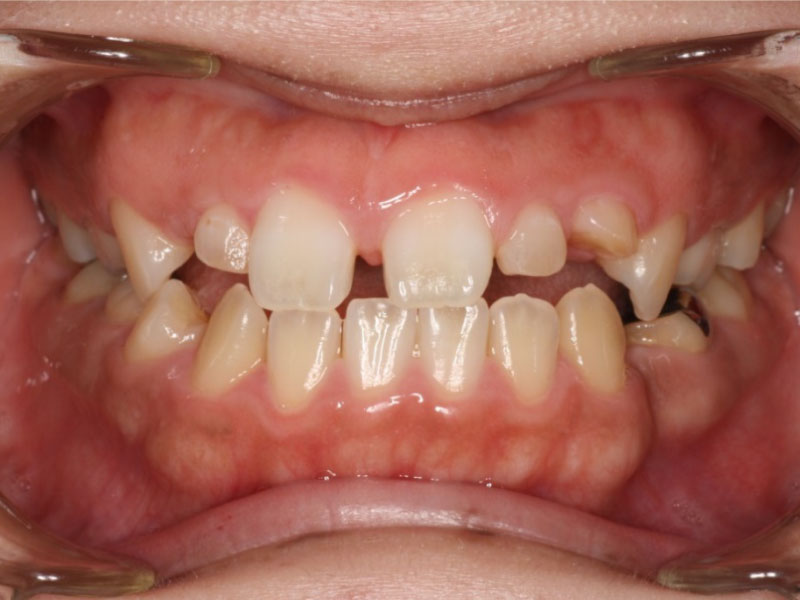

▼ ケース5 下顎前歯部叢生症例

初診時口腔内写真

初診時X線写真

治療終了時

before

after